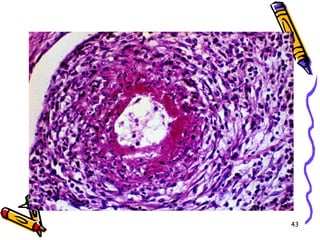

Mikroskopi

• Lezyonlar keskin sınırlı ve segmentaldir

• Fibrinoid nekrozla birlikte lökositik

inflamasyon ve tromboz

• İnflamasyon nedeni ile duvarda zayıflama

ve anevrizmal dilatasyon

• Damarın beslediği dokularda infarktüs,

atrofi, hemoraji